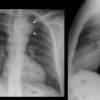

Phình ĐM chủ

» Thông tin: Nam giới – 45 tuổi.

» Lâm sàng: Đau ngực.